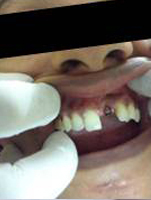

Placement of Abutement

Single Tooth Implant